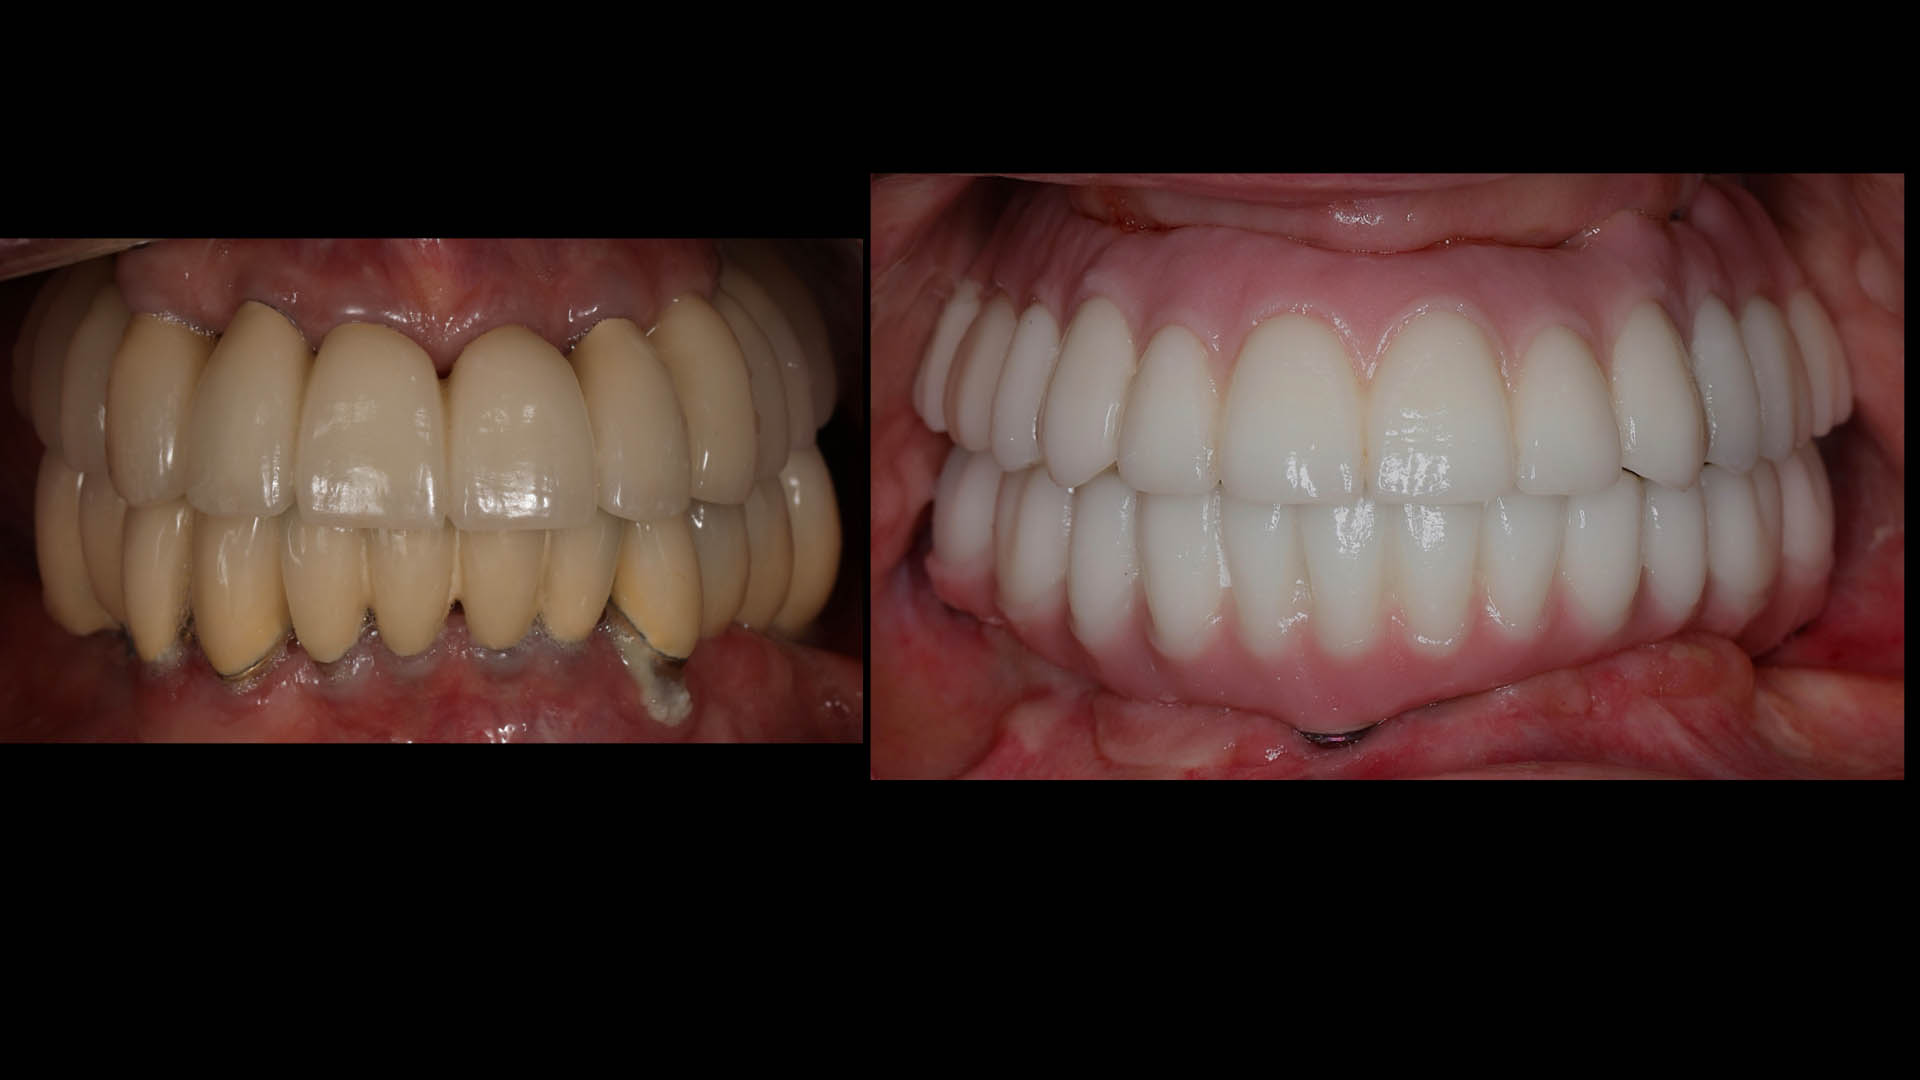

Take a glimpse into the magic of Coral Gables Dentistry through our before and after pictures. See firsthand the incredible smile makeover transformations that have brought confidence and joy to our patients.